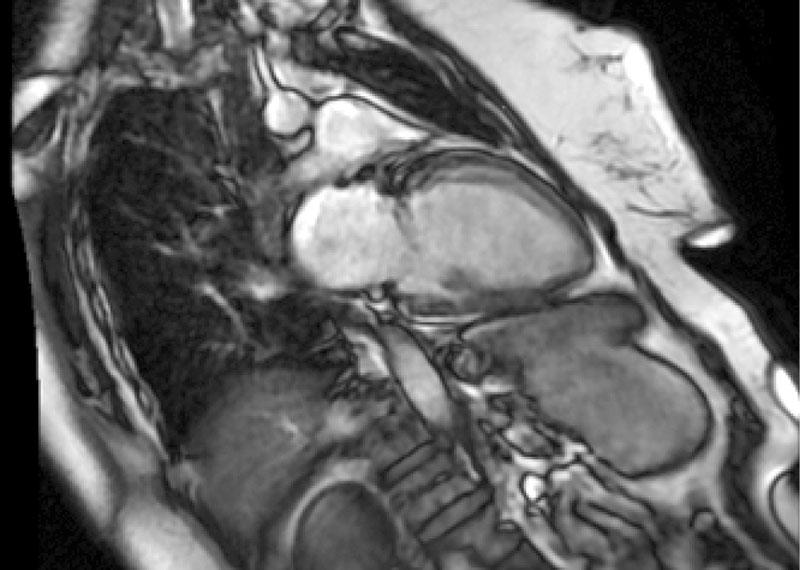

Рис. 1. Эхокардиография: выраженная недостаточность митрального клапана на момент поступления

По данным ЭхоКГ: отмечается фиброз створок митрального клапана, отрыв хорд задней створки митрального клапана с формированием регургитации 3-й степени (рис. 1), фиброз створок легочного клапана, пиковое давление в стволе легочной артерии – 50 мм рт. ст., фиброз створок аортального и трикуспидального клапанов без нарушения гемодинамики, отмечается дилатация полости левого предсердия – до 97 мл, объемы левого желудочка (ЛЖ) – в пределах нормы, локальная сократимость и глобальная функция ЛЖ – не нарушены, фракция выброса – 66%, диастолическая дисфункция ЛЖ 2-го типа, объемы правых камер сердца – не увеличены. По результатам селективной коронарной ангиографии, гемодинамически значимого поражения коронарных артерий не выявлено. В качестве дообследования выполнена магнитно-резонансная томография сердца с внутривенным контрастированием, по результатам которой выявлен протяженный фиброз миокарда ЛЖ в базальных, средних и верхушечных отделах – суммарно 6,8% (рис. 2).